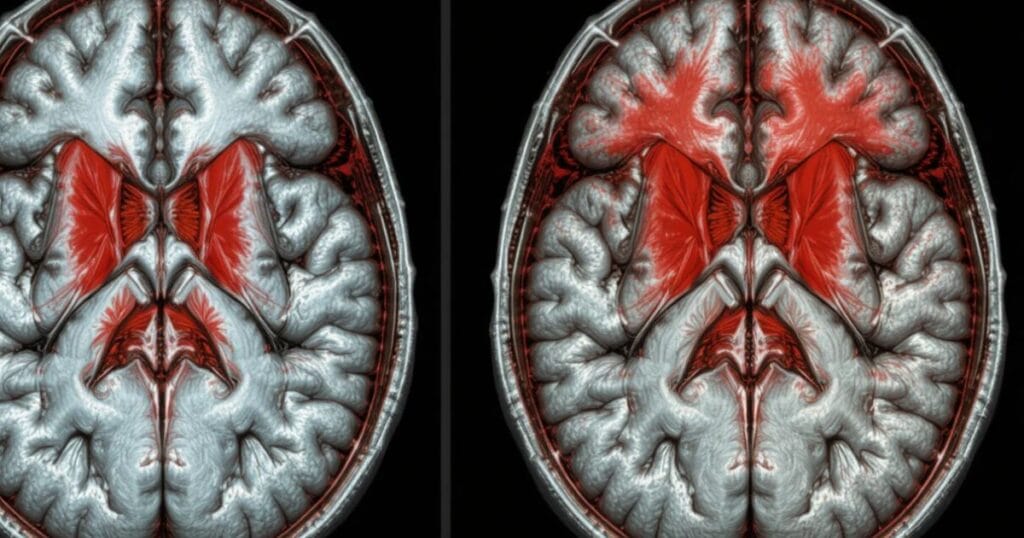

Each of these injuries may require advanced brain scans after car accident such as CT or MRI to detect hidden damage.

How Doctors Diagnose Head Trauma

Doctors use various neurological tests and imaging techniques to assess the severity of head trauma. They evaluate pupil reaction, memory, balance, and speech.

A brain scan / CT / MRI helps detect brain hemorrhage car crash, contusions, or swelling. These advanced tools allow healthcare providers to create accurate treatment plans tailored to each patient.